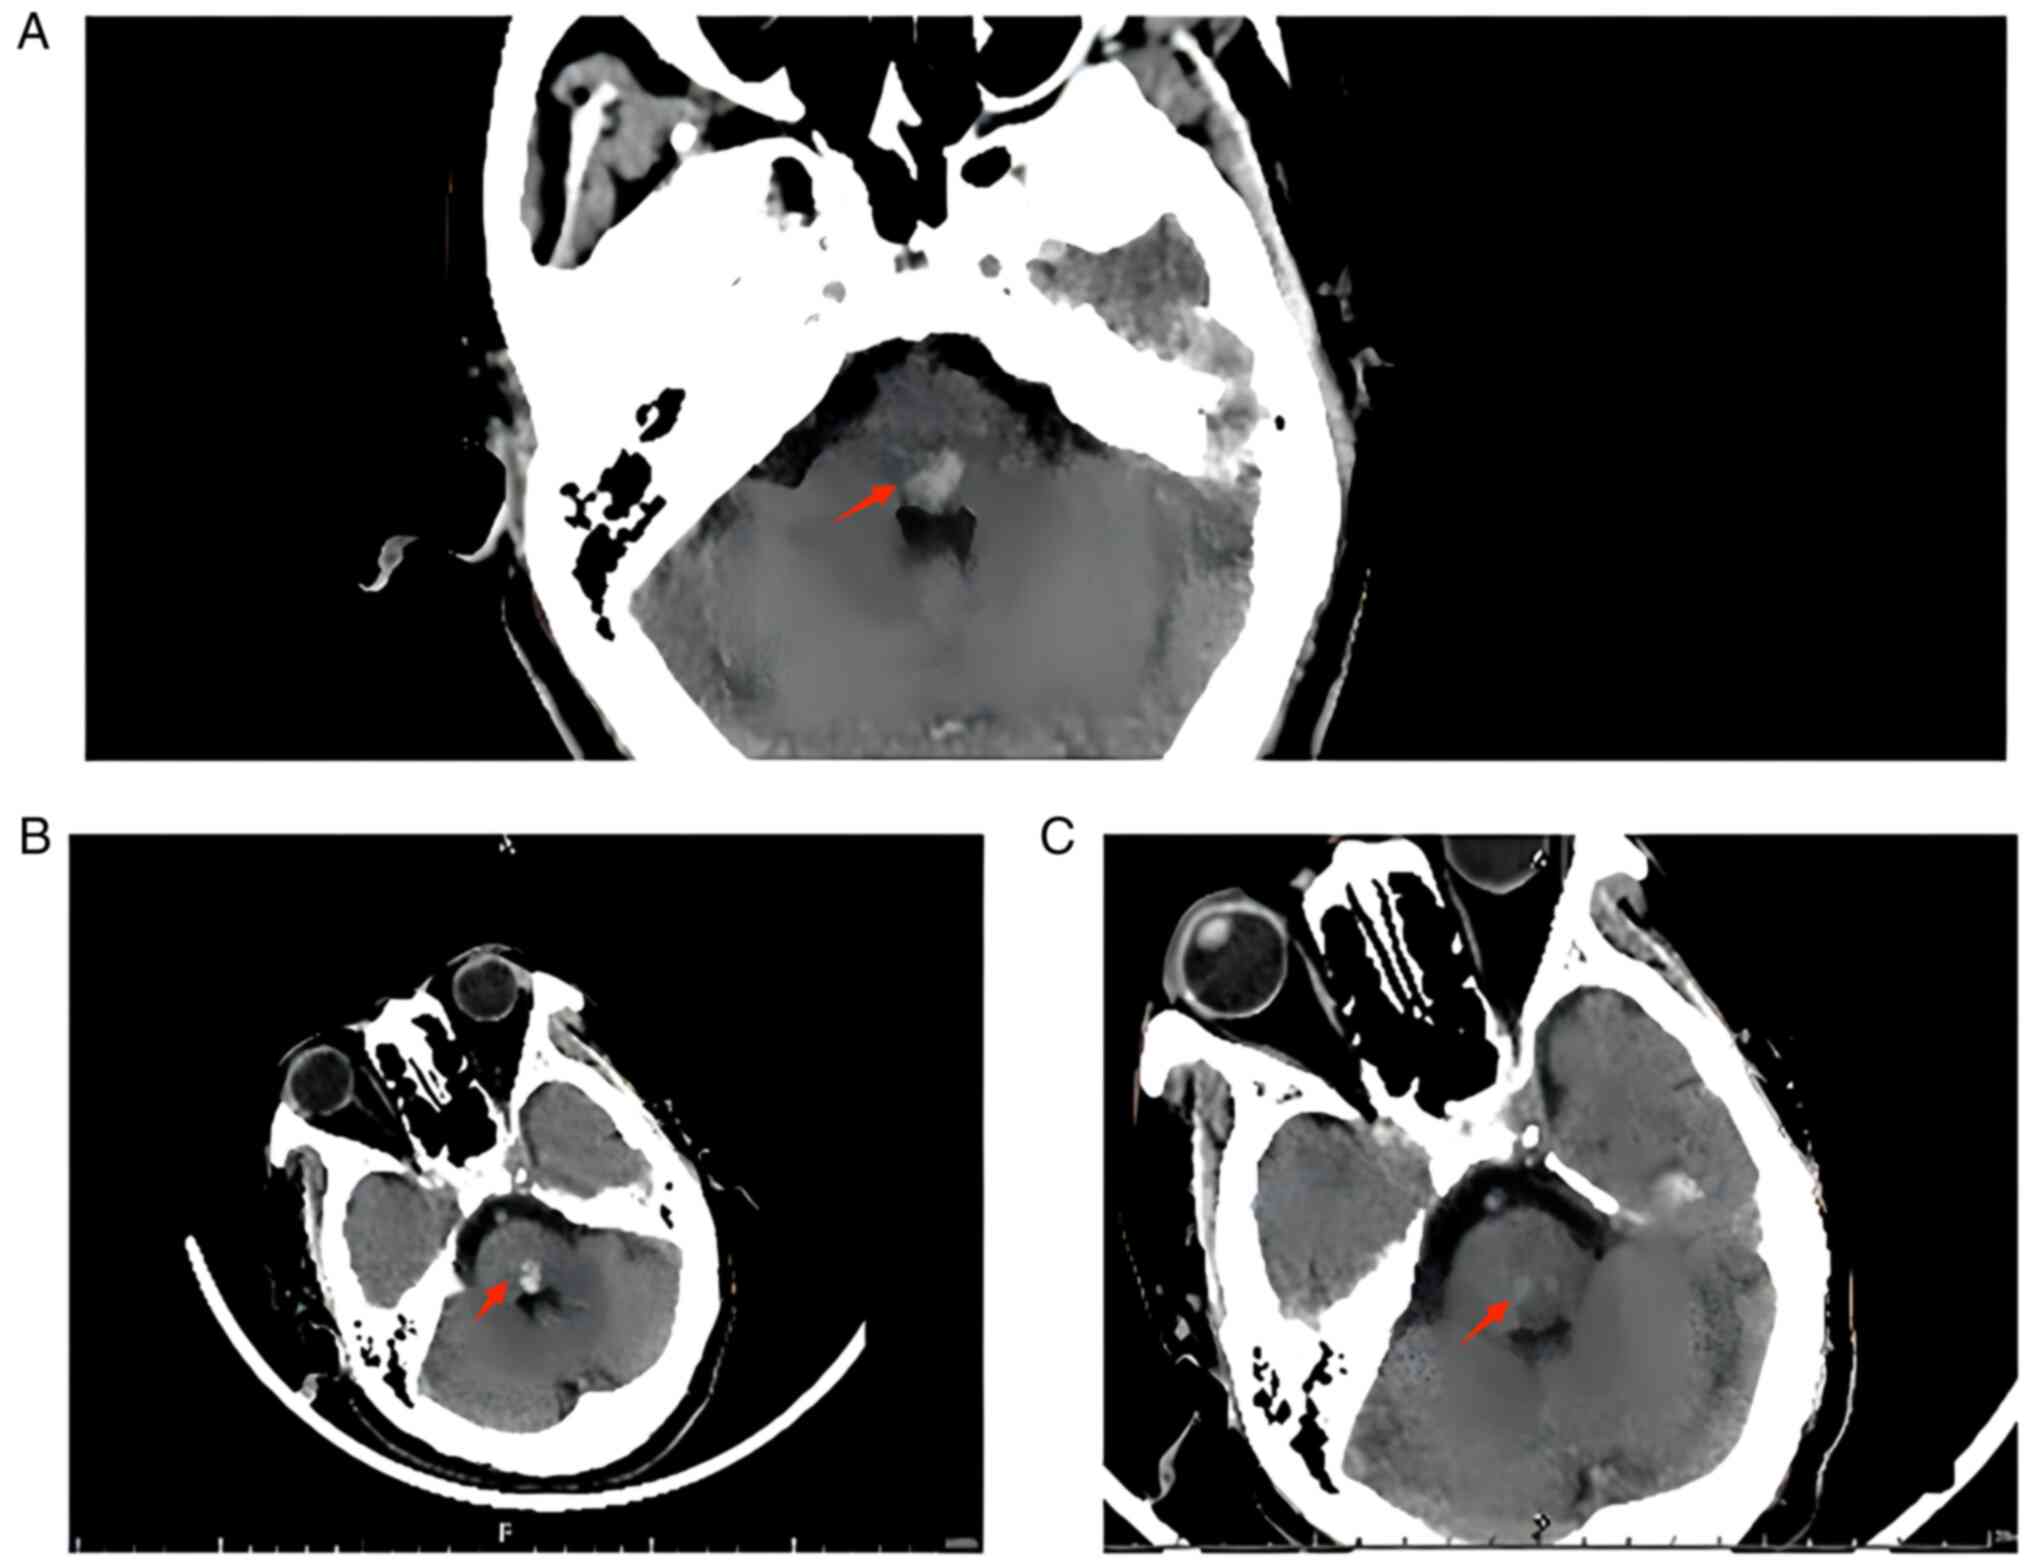

On 14th May 2022, the patient had a sudden onset of weakness and numbness in the right limb during sleep at night, which was accompanied by blurred and double vision, without consciousness or limb movement disorder, and his BP was 186/105 mmHg. Physical examination showed normal muscle strength of the upper right limb and grade IV muscle strength of the lower right limb. Bilateral pathological signs were absent. Urgent cranial computed tomography (CT) (Fig. 1A) showed high-density brainstem shadow, and brainstem haemorrhage was considered. The neurosurgery department was therefore consulted, and the patient was suspected to have a brainstem haemorrhage of <5 ml. Since the patient was conscious and did not have any limb movement disorder, surgery was contraindicated; instead, bed rest and symptomatic antihypertensive treatment were recommended. The patient was treated with absolute bed rest, active BP monitoring to decrease BP, intravenous infusion of glycerol fructose and tranexamic acid, regular HD three times a week, and anticoagulation with citrate during HD.

Figure 1

(A) Brain CT on 14th May 2022 showed patchy high density in the brainstem with clear borders, which was considered to be a haemorrhage. (B) Brain CT on 17th May showed patchy high density in the brainstem with clear borders, which was considered to be a haemorrhage slightly increased compared with that of 14th May. (C) Brain CT on 27th May showed patchy high density in the brainstem with clear borders, which indicated that the haemorrhage appeared to be decreasing in extent and had a reduced density compared with that of 17th May. The red arrow shows the haemorrhage site. CT, computed tomography.

On 17th May, re-evaluation via cranial CT (Fig. 1B) showed that the area of brainstem high density was slightly larger than that observed in the previous scan. In addition, the patient experienced more discomfort, which was accompanied by intermittent drowsiness. However, he did not have any limb movement disorder, and he received intravenous infusion of human serum albumin and diuretic therapy. On 21st May, his condition improved, since the weakness and numbness on the right side were significantly reduced, and he did not have double vision. However, the patient refused to undergo cranial CT owing to personal reasons. Glycerol fructose infusion was discontinued, but the rest of the treatment continued to be the same. On 27th May, cranial CT (Fig. 1C) showed high density in the brainstem, which was significantly lower than that previously observed. Although the patient had numbness in the right limb, he did not have other symptoms of discomfort, and could walk normally.